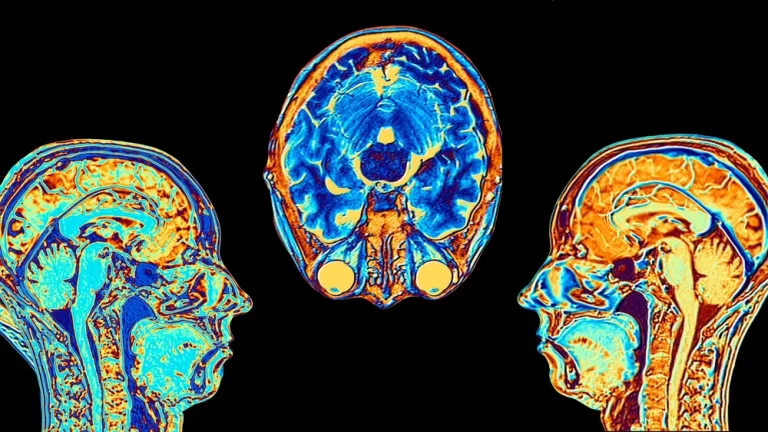

¿Sabías que la neurociencia ha comenzado a explicar las diferencias entre el cerebro optimista y el pesimista?...